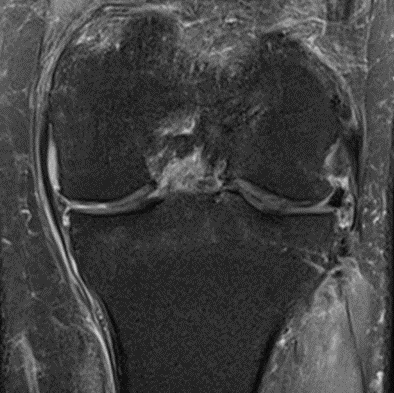

MRI scans illustrating the improvements regarding Group 2 are presented below, showing pre-treatment images with evident cartilage defects, pronounced bone marrow edema, and synovial inflammation, followed by post-treatment scans demonstrating improved joint structure, reduced edema, and decreased inflammation (Figures 12-29).

MRIs of Group 2

Figure 18: Female, 77 years, pre-intervention MRI.

Figure 19: Female of figure 18, two-month follow-up MRI: MSC plus ChondroFiller® liquid.